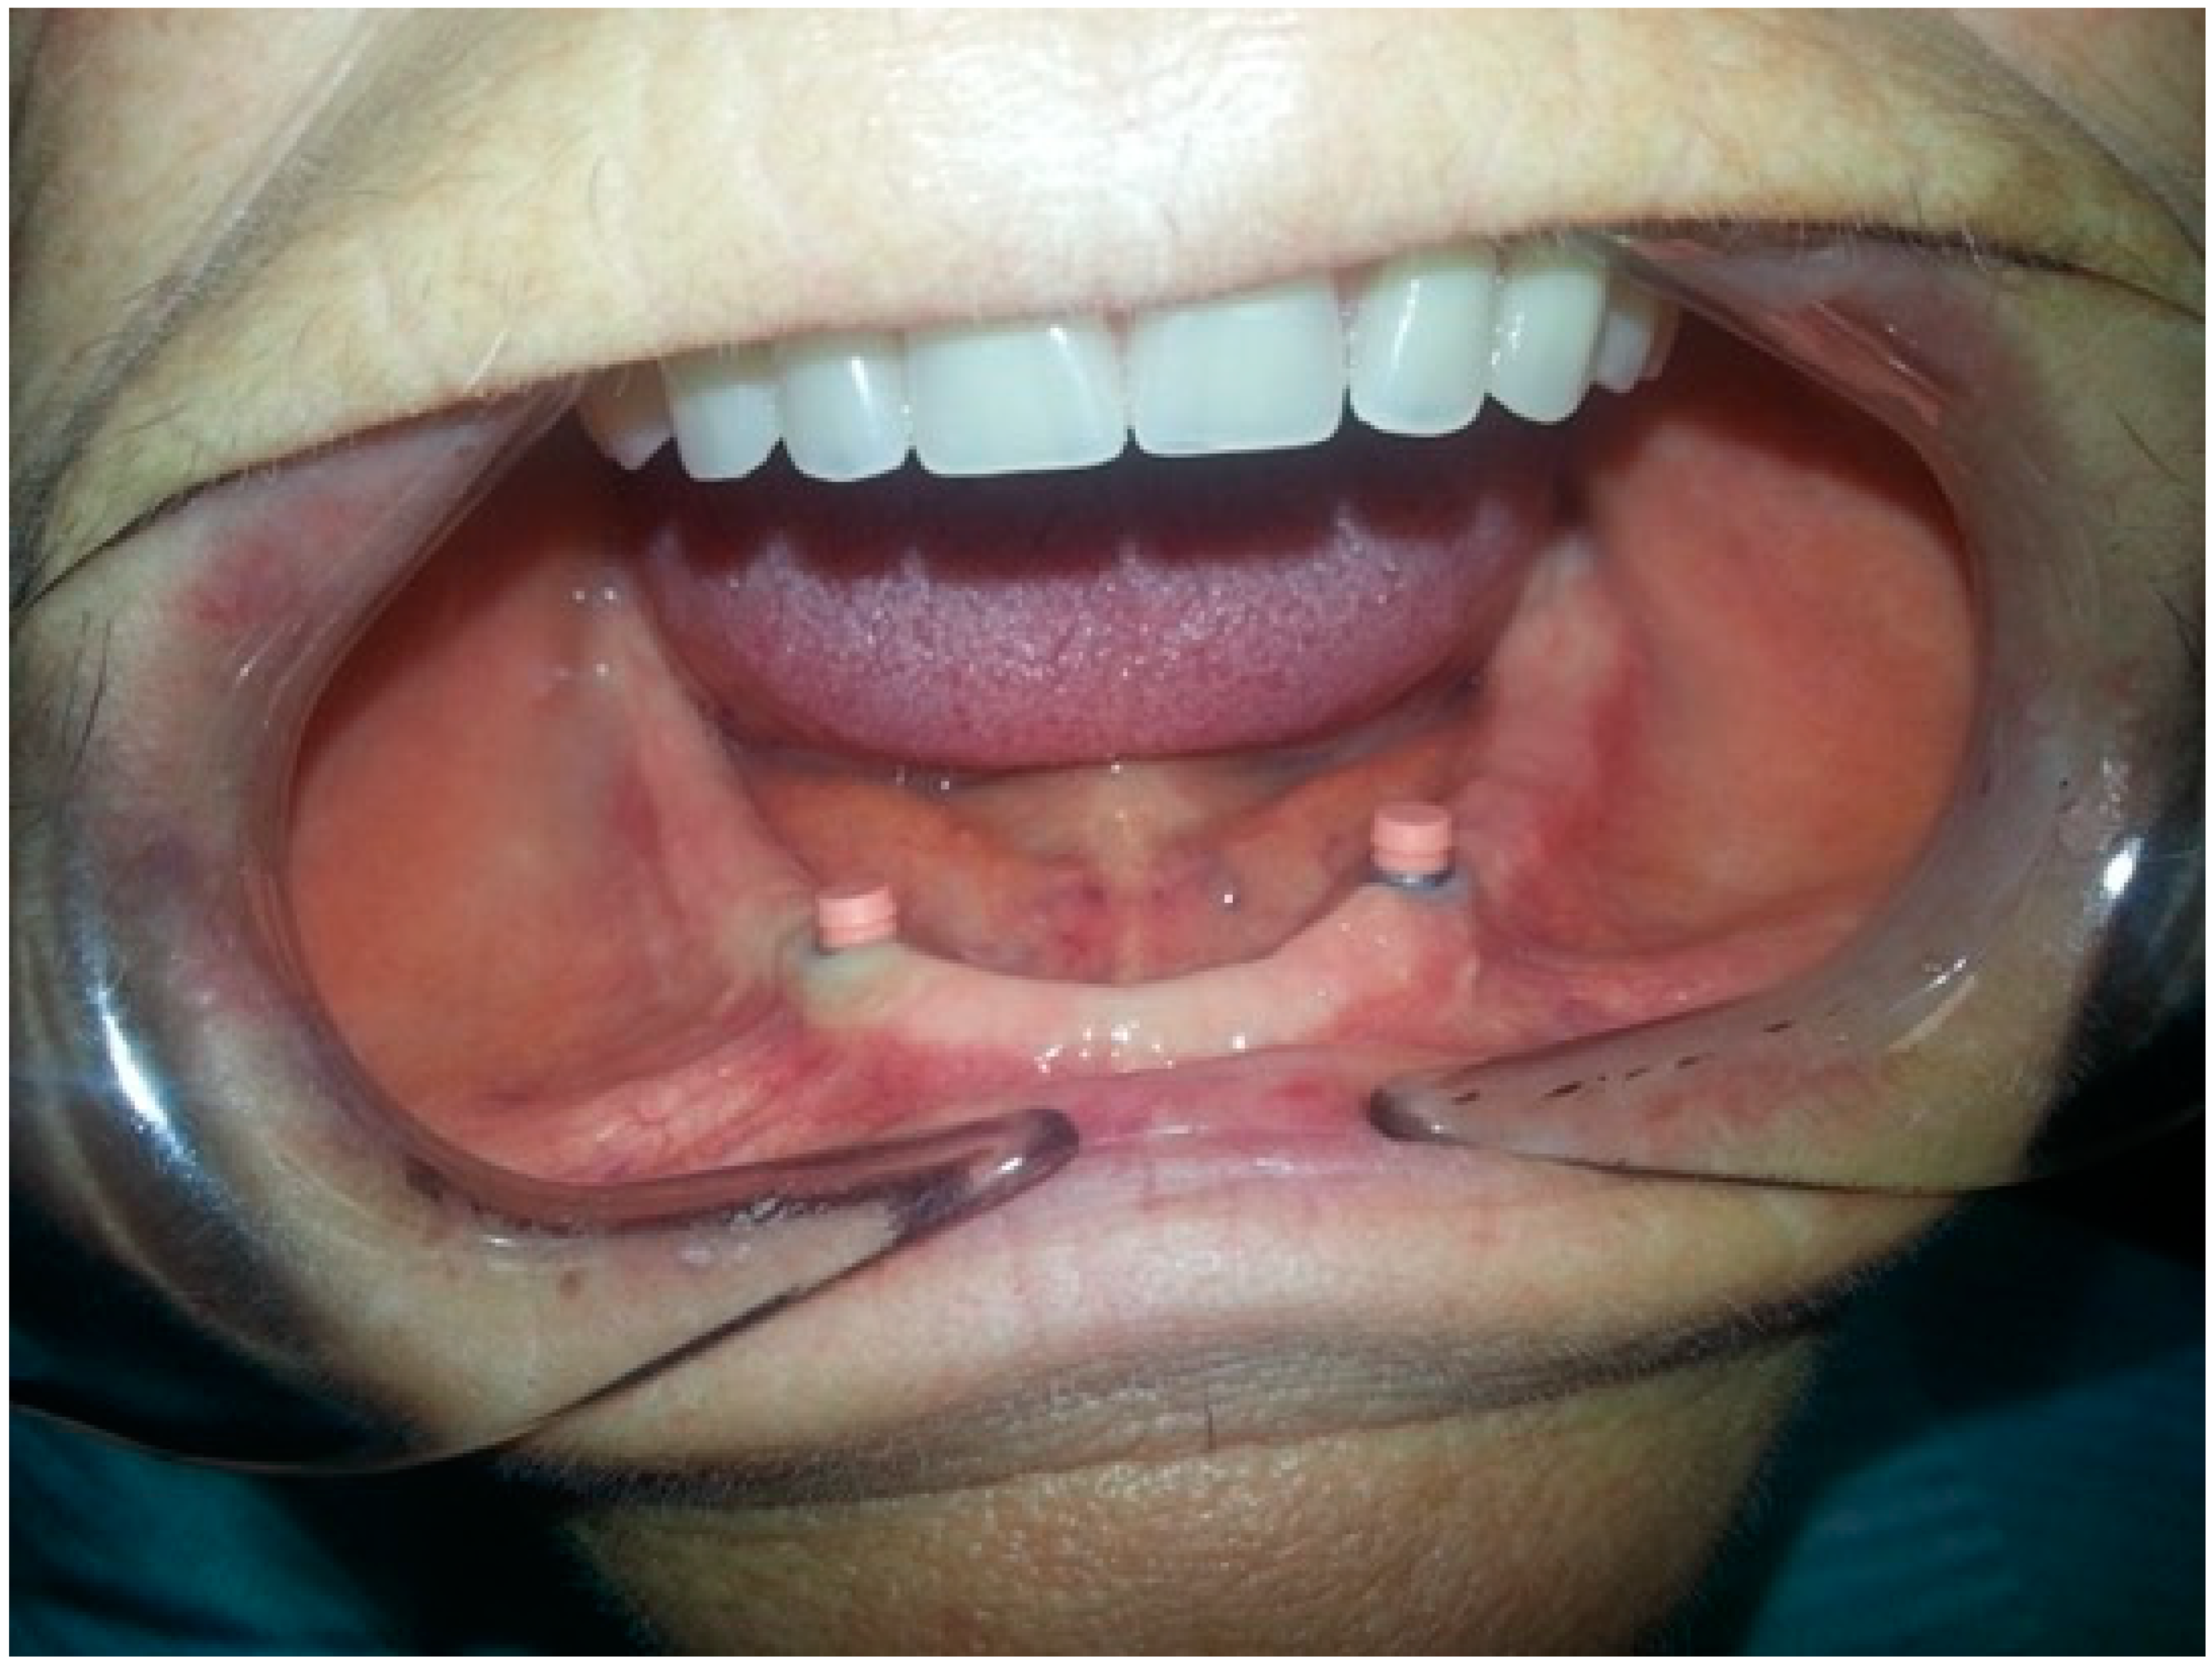

- After 7 days, the Teflon/o-ring is replaced. After preparing the housing for the Teflon on the mobile prosthesis and evaluating the necessary height, insert the small silicone tube cut at the right height in the ball-attachment. Then, the Teflon is inserted. The silicone tube adheres superiorly to the Teflon inferiorly to the gingiva protecting the entire retentive attachment (Figure 4, Figure 5, Figure 6 and Figure 7). After mixing the acrylic resin and inserting it in the right quantity (filling the previously prepared cavity 50%), the prosthesis is fitted into the oral cavity, causing the patient to close in full intercuspidation and waiting for polymerization (Figure 8, Figure 9 and Figure 10). Once the polymerization has taken place, the mobile prosthesis can be removed very easily as the acrylic resin will be present only around the Teflon and will have filled all the walls of the cavity previously prepared leaving them smooth; there may be small smears of resin that will easily be removed in a short time with the aid of rubber pads (Figure 11).